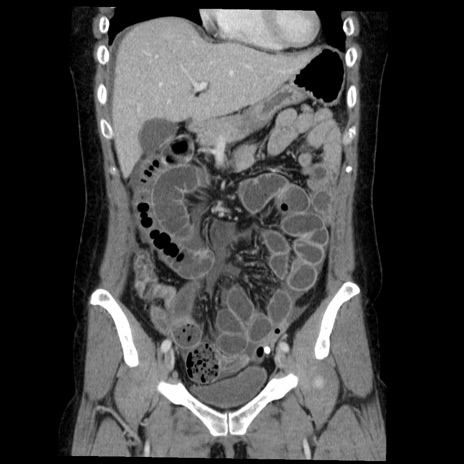

症例6(冠状断像)

【症例】50歳代女性

【主訴】下腹部痛

【現病歴】本日朝より下痢2回あり。 昼食を食べた後、嘔吐3回、下腹部痛認め、症状軽快せず、当院救急搬送。

最終食事:本日昼(生ものなし)。 昨日の夜、刺身を食ぺたとのこと。周囲に同様の症状の者なし。普段、排便は毎日あるとのこと。

【既往歴】卵巣癌術後(8年前に当院で卵巣摘出)

【身体所見】 意識清明、腹部:平坦、腸蠕動音→、やや硬、下腹部自発痛・圧痛あり、反跳痛あり、筋性防御なし。

【データ】WBC 16000、CRP 0.01